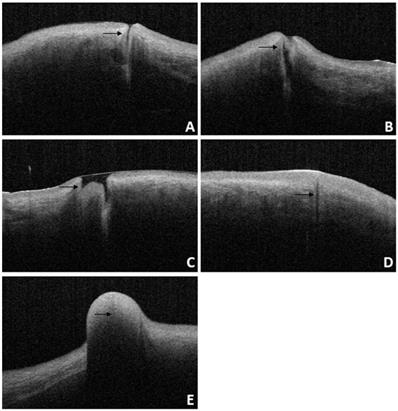

Figure 9

OCT image of lacrimal lesions. A: punctal stenosis, B: punctal obstruction, C: punctal tear, D: punctal atresia, E: punctal mass.

For patients diagnosed with punctal stenosis, OCT showed that the opening of the lacrimal punctum was narrow and small, and the lumen of the vertical canaliculus looked like a fissure. In the case of patients diagnosed with punctal obstruction, OCT showed that the opening of the lacrimal punctum was shielded by a banded membrane-like material, one end was connected to the lacrimal wall, while the other was suspended near the opening of the punctum. Furthermore, the vertical canaliculus was visible. In patients diagnosed with punctal tear, the lacrimal punctum had an abnormal shape, and the opening was larger than normal. In cases of punctal atresia, punctal openings were not observed in either eye, while the lumens of the inferior vertical canaliculi were visible in two eyes. Furthermore, the lacrimal punctum and vertical canaliculus were not observed in one eye. For the patient with a mass in the punctum, OCT showed a bulge with a high and medium reflection on the lacrimal punctum without a normal punctum and vertical canalicular structure (Fig. 8, 9).